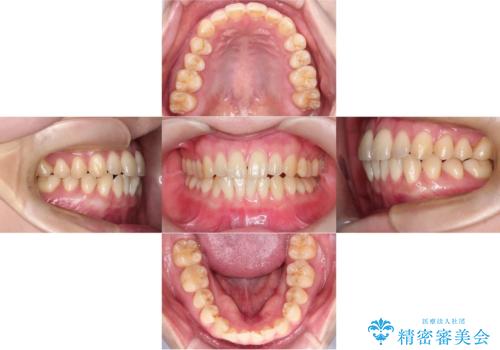

- 「下の前歯が斜めになっている」を主訴に来院された患者様です。

下顎前歯に叢生があり、右上2は反対咬合の状態でした。

下顎前歯の叢生がとれ右上2の反対咬合も改善し患者様にも満足していただけました。治療期間は1年~1年半を見込んでいましたが、患者様の協力もあり10か月で矯正を終えることが出来ました。

インビザラインはご自身でマウスピースをはめて頂く矯正なので、マウスピースの使用時間をきちんと守れているかどうかがとても大事になります。

インビザラインの性質上、食いしばりや歯ぎしりがある方は咬み合わせが甘くなることがあります。そのような時は保定装置にベックタイプのリテーナーを組み合わせることで改善できます。